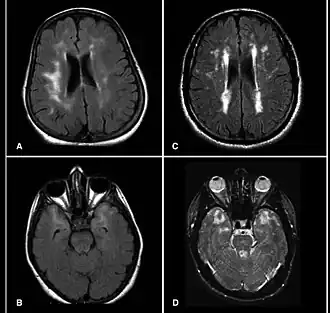

![]() Imagen MRI del cerebro de pacientes con CADASIL mostrando lesiones múltiples | ||

El método preferido de diagnóstico es la resonancia magnética. Las lesiones detectables con este sistema se encuentran concentradas alrededor de los ganglios basales, la sustancia blanca periventricular y el puente de Varolio, y son similares a las que se pueden observar en la enfermedad de Binswanger. Las lesiones en la sustancia blanca suelen estar presentes también en individuos que sufren la mutación del gen en cuestión sin presentar síntomas (Tournier et al, 1993). Otro diagnóstico diferencial a tener en cuenta es la esclerosis múltiple.